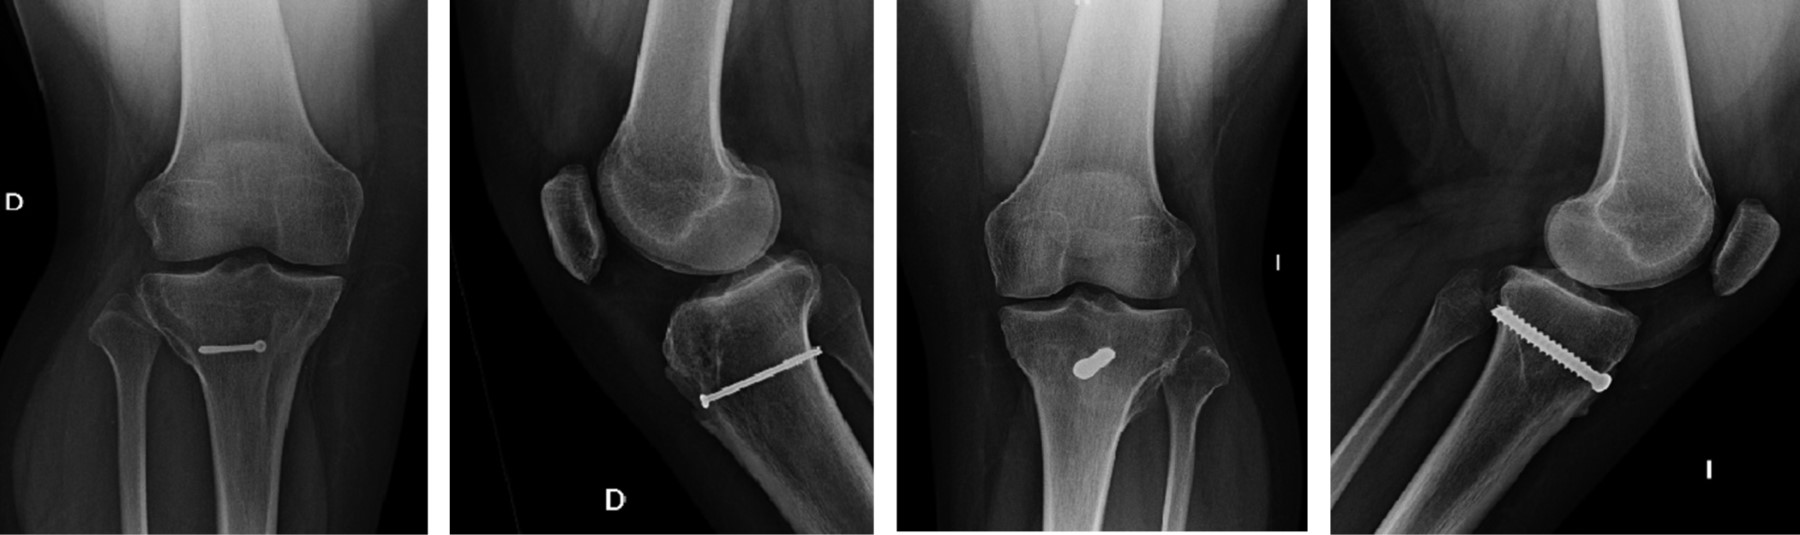

Treatment of a bilateral fracture of the anterior tubercle of the tibia in an adolescent

Fractures of the anterior tubercle of the tibia are rare pathologies that mainly affect male adolescent patients, related to sports activity, predominantly in activities that involve jumping. In patients with advanced skeletal development, the physis can be crossed by internal fixation elements; on the contrary, if the patient presents immature bone growth, we should not cross the physis because the growth cartilage could be affected. A case of an 15-year-old patient which presents a bilateral fracture of the anterior tuberosity of the tibia posterior of a fall after a low-energy jump, the patient is evaluated and treatment is indicated, with good results, in the case clinical and radiographic characteristics are described and the surgical resolution.

Figure 1

Figure 2

Figure 3

Figure 4

Figure 5